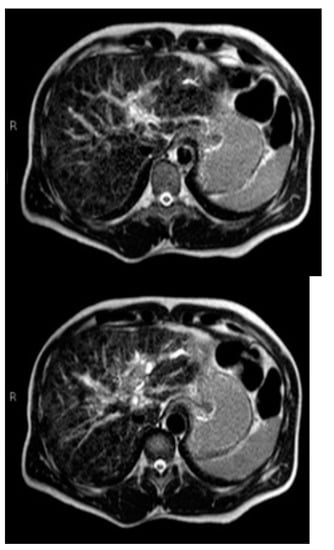

Subsequently, an upper-abdomen Computed Tomography (CT) scan and liver Magnetic Resonance Imaging (MRI) were performed (Figure 1, Figure 2, Figure 3, Figure 4, Figure 5, Figure 6 and Figure 7).

Figure 6.

MRI arterial, portal, and HPB phases.

A mass of 1.8 cm was detected within the biliary branch for the third hepatic segment, characterized by nodular impregnation in the arterial phase and irregular and partial washout in the portal venous phase. These findings were compatible with a heterologous lesion, although it was not possible to perform a diagnosis among HCC, intrahepatic CCA or other pathological lesions.

HCC typically has an increased arterial blood supply, so it usually shows hyperattenuation in the arterial phase and hypoattenuation in the portal venous phase, compared to the hepatic parenchyma.

Most HBDTTs should show the same enhancement pattern. However, some HCCs can show iso- or hypoattenuation in the arterial phase, with the enhancement in the arterial phase inversely correlated with the degree of blood clots and necrosis. So, hypoattenuation in the portal venous phase seems to be the most important imaging feature to distinguish HCC with BDTT from perihilar CCA [17].

Washout in the portal venous phase is also the main feature to distinguish HCC with BDTT from intrahepatic CCA, together with the presence of tortuous tumoral vessels [17].

In conclusion, the diagnosis of HCC with BDTT can be reasonably considered in the presence of lesions of both hepatic parenchyma and bile ducts with a cirrhotic underlined liver disease, especially if they show typical washout in the portal venous phase.